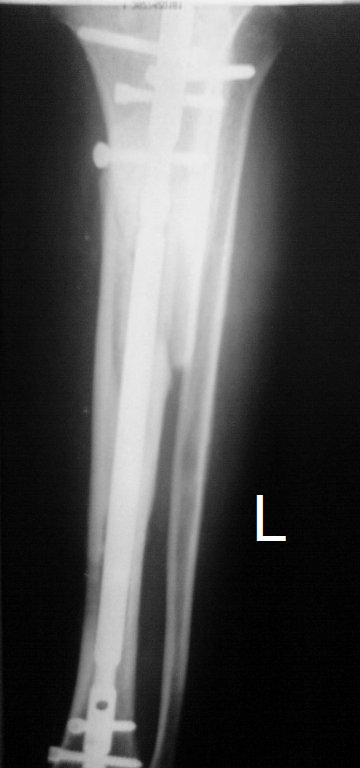

Итак, в настоящий момент больной пришел к нам с полной нагрузкой на оперированную конечность и с такой картиной

(см. приложение). Участок мягких тканей, с передней стенкой  нижней трети ББК, выгнил и представляет дефект

2×2,5 см. На перевязке - циркулярный(?) некроз костной трубки.

Вложение не в текстовом формате было извлечено…

Имя     : tibAP01.JPG

Тип     : image/jpeg

Размер  : 30590 байтов

Описание: отсутствует

Url     : http://weborto.net:8080/pipermail/ortho/attachments/20091123/dddb0a2c/attachment-0013.jpeg